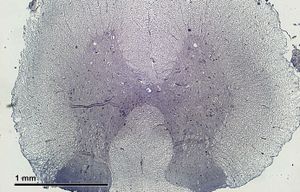

신경조직은 신경세포체와 축삭의 분포에 따라 회색질과 백색질로 구분된다.

중추신경계에서 신경세포체가 모여 있는 부분은 비교적 짙게 보여 회색질이라고 부르고, 축삭이 모여 있는 부분은 미엘린 때문에 희게 보이므로 백색질이라고 부른다. 회색질에는 신경세포체와 가지돌기가 있으므로 시냅스도 대부분 이곳에서 이루어진다. 축삭, 가지돌기 및 신경아교세포 돌기들이 어지럽게 얽혀 신경그물(neuropil)을 이룬다. 백색질에는 축삭, 신경아교세포, 혈관이 있으며 신경세포체는 존재하지 않는다. 백색질의 축삭 가운데 출발 지점과 도착 지점이 서로 비슷해 구조적, 기능적으로 밀접하게 연관되어 있는 것들을 묶어 신경로라고 일컫는다.[22]

회색질과 백색질의 배열 양상은 부위에 따라 다르게 나타난다. 척수에서는 회색질이 안쪽, 백색질이 바깥쪽에 위치한다. 대뇌와 소뇌에서도 중심부에 바닥핵(기저핵)이라는 회색질 덩어리들이 존재하고 백색질이 그 주변을 둘러싸고 있지만, 척수와 달리 가장 표면 부위에 추가적으로 회색질 층이 있어서 대뇌겉질 및 소뇌겉질을 형성한다. 뇌줄기에서는 회색질과 백색질을 구분하기 어렵다.[22]

3. 1. 회색질과 백색질

회색질은 신경세포체, 가지돌기, 무수축삭, 신경아교세포 등이 모여 있는 영역으로, 주로 정보 처리를 담당한다. 백색질은 유수축삭, 신경아교세포 등이 모여 있는 영역으로, 신경세포 간의 정보 전달 통로 역할을 한다. 뇌와 척수에서 회색질과 백색질의 배열 양상이 다르다.[22]척수에서는 회색질이 안쪽에, 백색질이 바깥쪽에 위치한다. 대뇌와 소뇌에서도 중심부에 바닥핵(기저핵)이라는 회색질 덩어리들이 존재하고 백색질이 그 주변을 둘러싸고 있지만, 척수와 달리 가장 표면 부위에 추가적으로 회색질 층이 있어서 대뇌겉질 및 소뇌겉질을 형성한다. 뇌줄기에서는 회색질과 백색질을 구분하기 어렵다.[22]